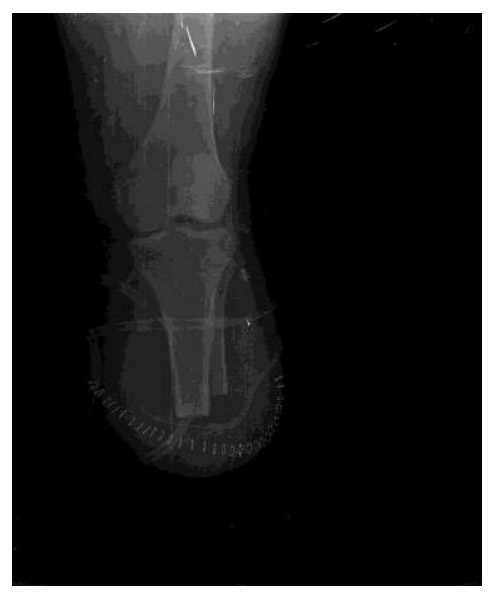

Ameliyat Sonrası: Röntgende diz altı amputasyon uygulandığı görülmekte